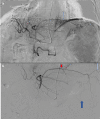

Figure 3

Figure 3. DSA angiogram from the left main hepatic artery demonstrating the anomalous branch (a, white arrow), and angiogram following selection of the anomalous branch with a microcatheter (b) demonstrating branches supplying the pericardium (red arrow), spleen (white arrow), and stomach (blue arrow).

DSA: digital subtraction angiography.